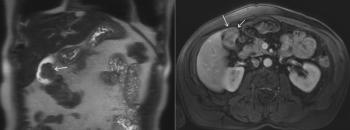

A 60-year-old woman presents with vague abdominal pain in the right upper quadrant. An ultrasound reveals a gallbladder abnormality. Based on the images from the abdomen MRI, what is the diagnosis?